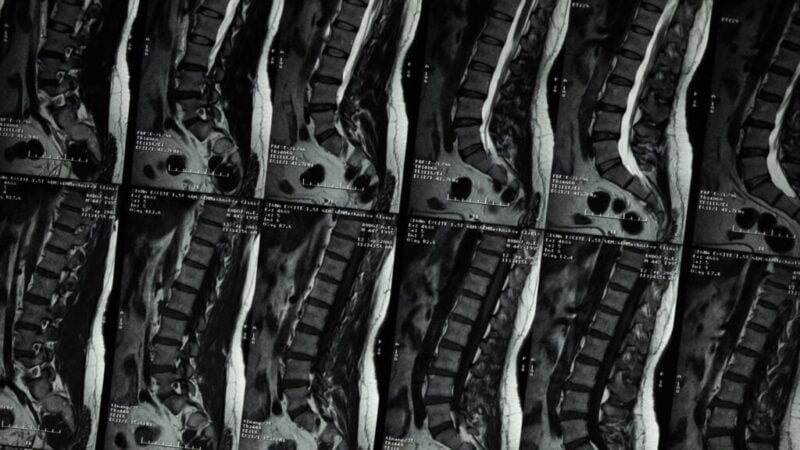

Imagens resultado de tomografia computadorizada da coluna para diagnóstico da artrose.

Para entender plenamente a artrose, é fundamental explorar as causas subjacentes que contribuem para o desenvolvimento dessa condição debilitante. A artrose é uma condição multifatorial, com vários fatores desencadeantes e contribuintes que desempenham papéis significativos em seu desenvolvimento. Causas da Artrose A principal causa da artrose é a degeneração da cartilagem articular. A cartilagem é … Ler mais